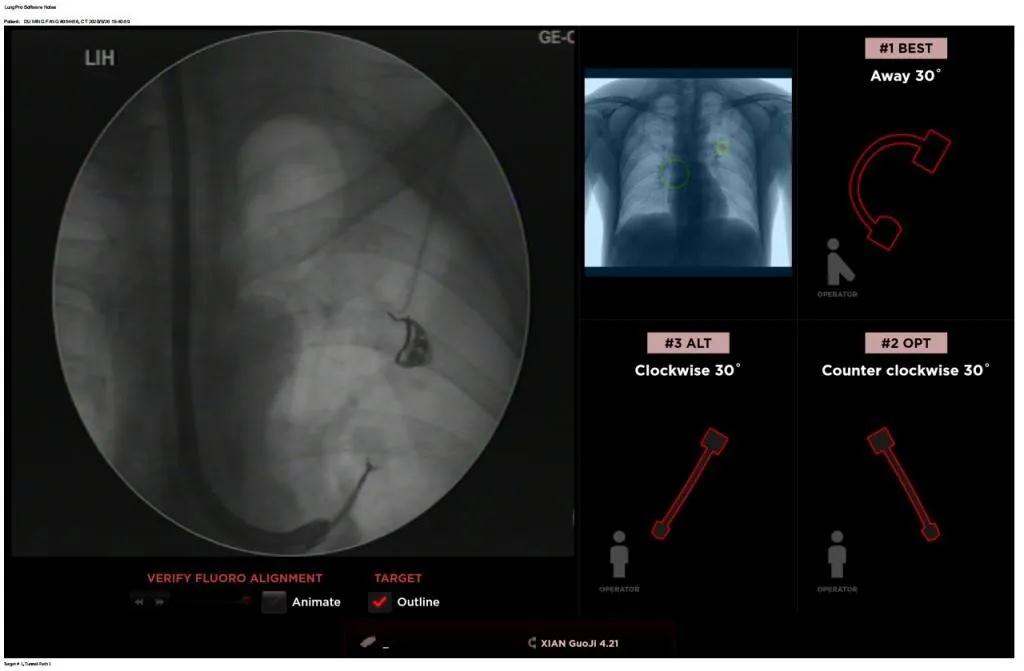

西安國際醫(yī)學(xué)中心醫(yī)院呼吸內(nèi)科完成西北地區(qū)首例LungPro全肺導(dǎo)航系統(tǒng)引導(dǎo)下BTPNA手術(shù)

近日,西安國際醫(yī)學(xué)中心醫(yī)院胸科醫(yī)院歐陽海峰副院長完成西北地區(qū)首例LungPro全肺導(dǎo)航系統(tǒng)引導(dǎo)下經(jīng)支氣管鏡跨肺實(shí)質(zhì)肺外周結(jié)節(jié)活檢術(shù)。

經(jīng)過充分的討論后,歐陽海峰副院長決定為患者實(shí)施LungPro全肺導(dǎo)航系統(tǒng)引導(dǎo)的經(jīng)支氣管跨肺實(shí)質(zhì)肺外周結(jié)節(jié)活檢術(shù)。Broncus導(dǎo)航系統(tǒng)LungPro具有全球領(lǐng)先獨(dú)創(chuàng)的BTPNA技術(shù)(支氣管鏡下跨結(jié)節(jié)抵達(dá)術(shù)),可以實(shí)現(xiàn)對(duì)氣道外周孤立性肺小結(jié)節(jié)的精準(zhǔn)定位,建立直接通往氣道外病變部位的通道,以實(shí)現(xiàn)全肺的診斷及后續(xù)治療。這項(xiàng)技術(shù)不僅彌補(bǔ)了現(xiàn)有支氣管鏡技術(shù)由于受限于病變部位是否有氣道可通向以及無法準(zhǔn)確定位病變部位而造成的較低診斷率,同時(shí)還彌補(bǔ)了CT引導(dǎo)下經(jīng)胸穿刺(TTNA)無法適用于某些特定部位如中央及肩胛骨等結(jié)節(jié)的問題,并且還避免了經(jīng)胸穿刺給患者帶來氣胸、出血的高風(fēng)險(xiǎn),可有效提高肺部結(jié)節(jié)及早期肺癌診斷陽性率,亦可用于早期肺癌的射頻消融或微波治療,具有微創(chuàng)、安全、同期雙肺診療等優(yōu)勢(shì)。

BTPNA技術(shù)整合了虛擬導(dǎo)航支氣管鏡VBN、氣道內(nèi)超聲r(shí)EBUS、TBNA、高壓球囊擴(kuò)張、X線輔助等多項(xiàng)三、四級(jí)呼吸內(nèi)鏡技術(shù)。歐陽海峰副院長有3000 TBNA、1000 rEBUS、500 VBN、800 球囊擴(kuò)張方面的技術(shù)積累,10年來個(gè)人每年完成三、四級(jí)呼吸內(nèi)鏡手術(shù)1200余例,這有效保障了BTPNA技術(shù)的順利開展。

團(tuán)隊(duì)術(shù)前進(jìn)行了精心的準(zhǔn)備,通過高分辨率CT建立了導(dǎo)航路徑,在麻醉科手術(shù)室的配合下,借助LungPro引導(dǎo)順利的確定了病灶部位、建立隧道并實(shí)施活檢,術(shù)后患者恢復(fù)順利出院。